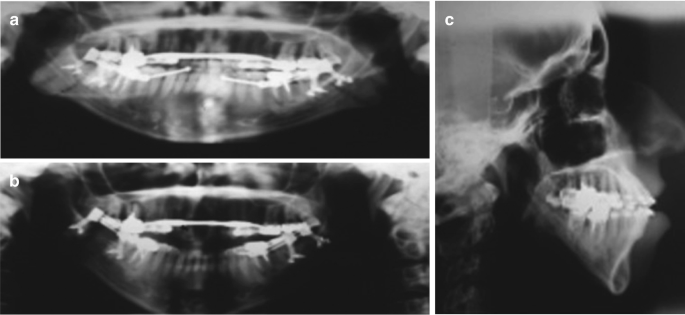

The patients chief complaint was that the upper right central incisor 8 was very loose in her upper jaw and she did not want to lose the tooth. Reasons for Jaw Bone Loss and Deterioration. X-ray of periostitis of the jaw.

On several occasions patient have come to me with the beginning of bone loss around the upper threads of dental implants a couple of years after they were restored. The best method to restore lost jawbone tissue is through bone grafting. 4 The wire used for the splint next to a perio probe.

Treating Dental Bone Loss. Note the vertical bone loss around 26. 1 3 Initial pictures and x-ray.

1 Upper right central incisor 8 has. The combination of the patients history and individual situation makes this a special case with regard to decision making and further therapy. Just like a muscle bone needs to.